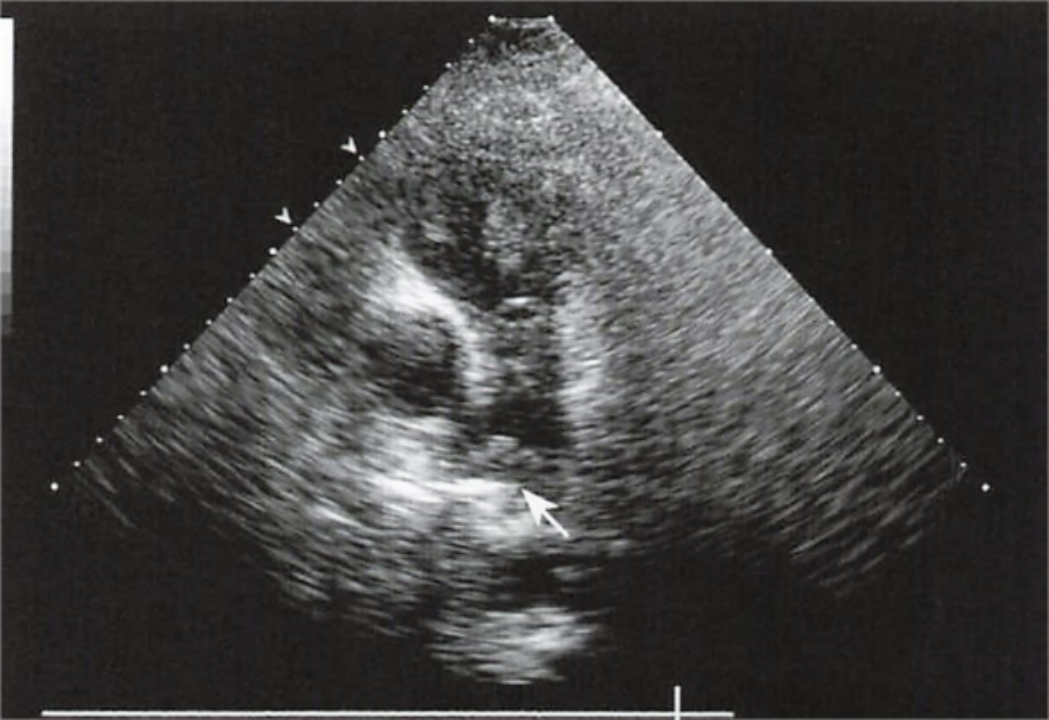

超声表示:

直接征象:

肺动脉近端或右心腔血栓。

肺动脉血栓

间接征象:

右心负荷过重的表现,如右心室壁局部运动幅度下降,右心室和(或)右心房扩大,三尖瓣反流、速度增快以及室间隔左移运动异常,肺动脉干增宽,肺动脉高压等。